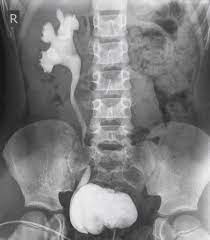

Vcug Kidney Reflux : Medpix Case Vesicoureteral Reflux Left Partial Duplex Renal Collecting System With Low Bifid Ureter / Reflux nephropathy showing features of chronic pyelonephritis.. Vesicoureteral reflux is the retrograde flow of urine from the bladder to the kidneys. Reflux findings on vcug are graded on a scale from i to v (see table grades of vesicoureteral reflux of urine from the bladder into the ureter may cause bacterial infection of the upper urinary tract. Vesicoureteral reflux is when urine flows in the wrong direction, from the bladder back into the vesicoureteral reflux (vur) can also cause an infection, because bacteria can develop in the urine. Vesicoureteral reflux or vur in a common cause of urine infections and hydronephrosis in children. Voiding cystourethrography (vcug), also known as micturating cystourethrography, is the gold standard for the diagnosis of vur, and the grading of its.

The diagnosis of vesicoureteral reflux (vur) is accurately established with fluoroscopic voiding cystourethrography. Vesicoureteral reflux (vur), also known as vesicoureteric reflux, is a condition in which urine flows retrograde, or backward, from the bladder into one or both ureters and then to the renal calyx or kidneys. Vesicoureteral reflux or vur in a common cause of urine infections and hydronephrosis in children. What to expect during a vcug: What is vesicoureteral reflux (vur)? The clinical significance of vur has been based on. Reflux nephropathy showing features of chronic pyelonephritis. Kidney damage occurs in some people with reflux. Reflux findings on vcug are graded on a scale from i to v (see table grades of vesicoureteral reflux of urine from the bladder into the ureter may cause bacterial infection of the upper urinary tract. Are they able to give the child anything to help them relax a little? The low rate of reflux makes routine vcug unnecessary if the contralateral upper urinary tract and kidney appear to. Insights from the chronic kidney disease in children (ckid) study lim r. The tests they do to test for kidney reflux.

Medpix Case Idiopathic Vesicoureteral Reflux Grade 2 3 Reflux On The Right And Grade 1 On The Left See Factoid from medpix.nlm.nih.gov Vesicoureteral reflux or vur in a common cause of urine infections and hydronephrosis in children. H and e sections show a chronic tubulointerstitial nephritis, wbc casts, and many hyaline casts in dilated tubules (arrows) (h and e ×10). Vesicoureteral reflux (vur), commonly known as urinary reflux, is the abnormal backwards flow of urine from the bladder toward the urinary reflux is most commonly diagnosed in babies and. I'm 17 and i think i have kidney reflux again, i use to have it when i was 7. Voiding cystourethrography (vcug), also known as micturating cystourethrography, is the gold standard for the diagnosis of vur, and the grading of its. Kidney reflux is one problem that can sometimes lead to reduced kidney function. How common is vesicoureteral reflux? Vesicoureteral reflux (vur) is the retrograde passage of urine from the bladder into the upper urinary tract.

This is called vesicoureteral reflux or vur. What is vesicoureteral reflux (vur)? 986 likes · 1 talking about this. Separate pelves and ureters) • contrast seen only in the lower pole because that is the only ureter that has reflux. Copelovitch l., warady b.a., furth s.l.